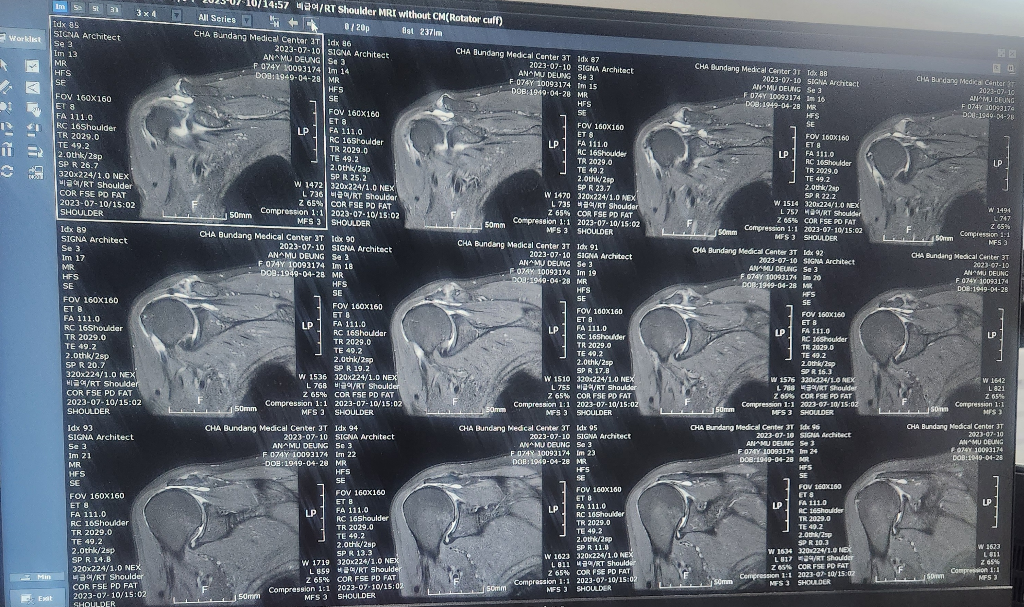

할머니가 넘어지면서 어깨를 다쳤는데

검사만하고 설명은 다음으로 미뤄져서요..

혹시 이 영상만으로 현재 어깨상태 문의드려도될까요

• 4번 째 사진

질환이 있다고 설명들은 특정 장면을 올려주시는 것이 아니라면 이런 식의 업로드로 영상을 보기가 힘듭니다. 잘 모르시겠다면 검사한 병원에서 설명을 들어보시기 바랍니다.